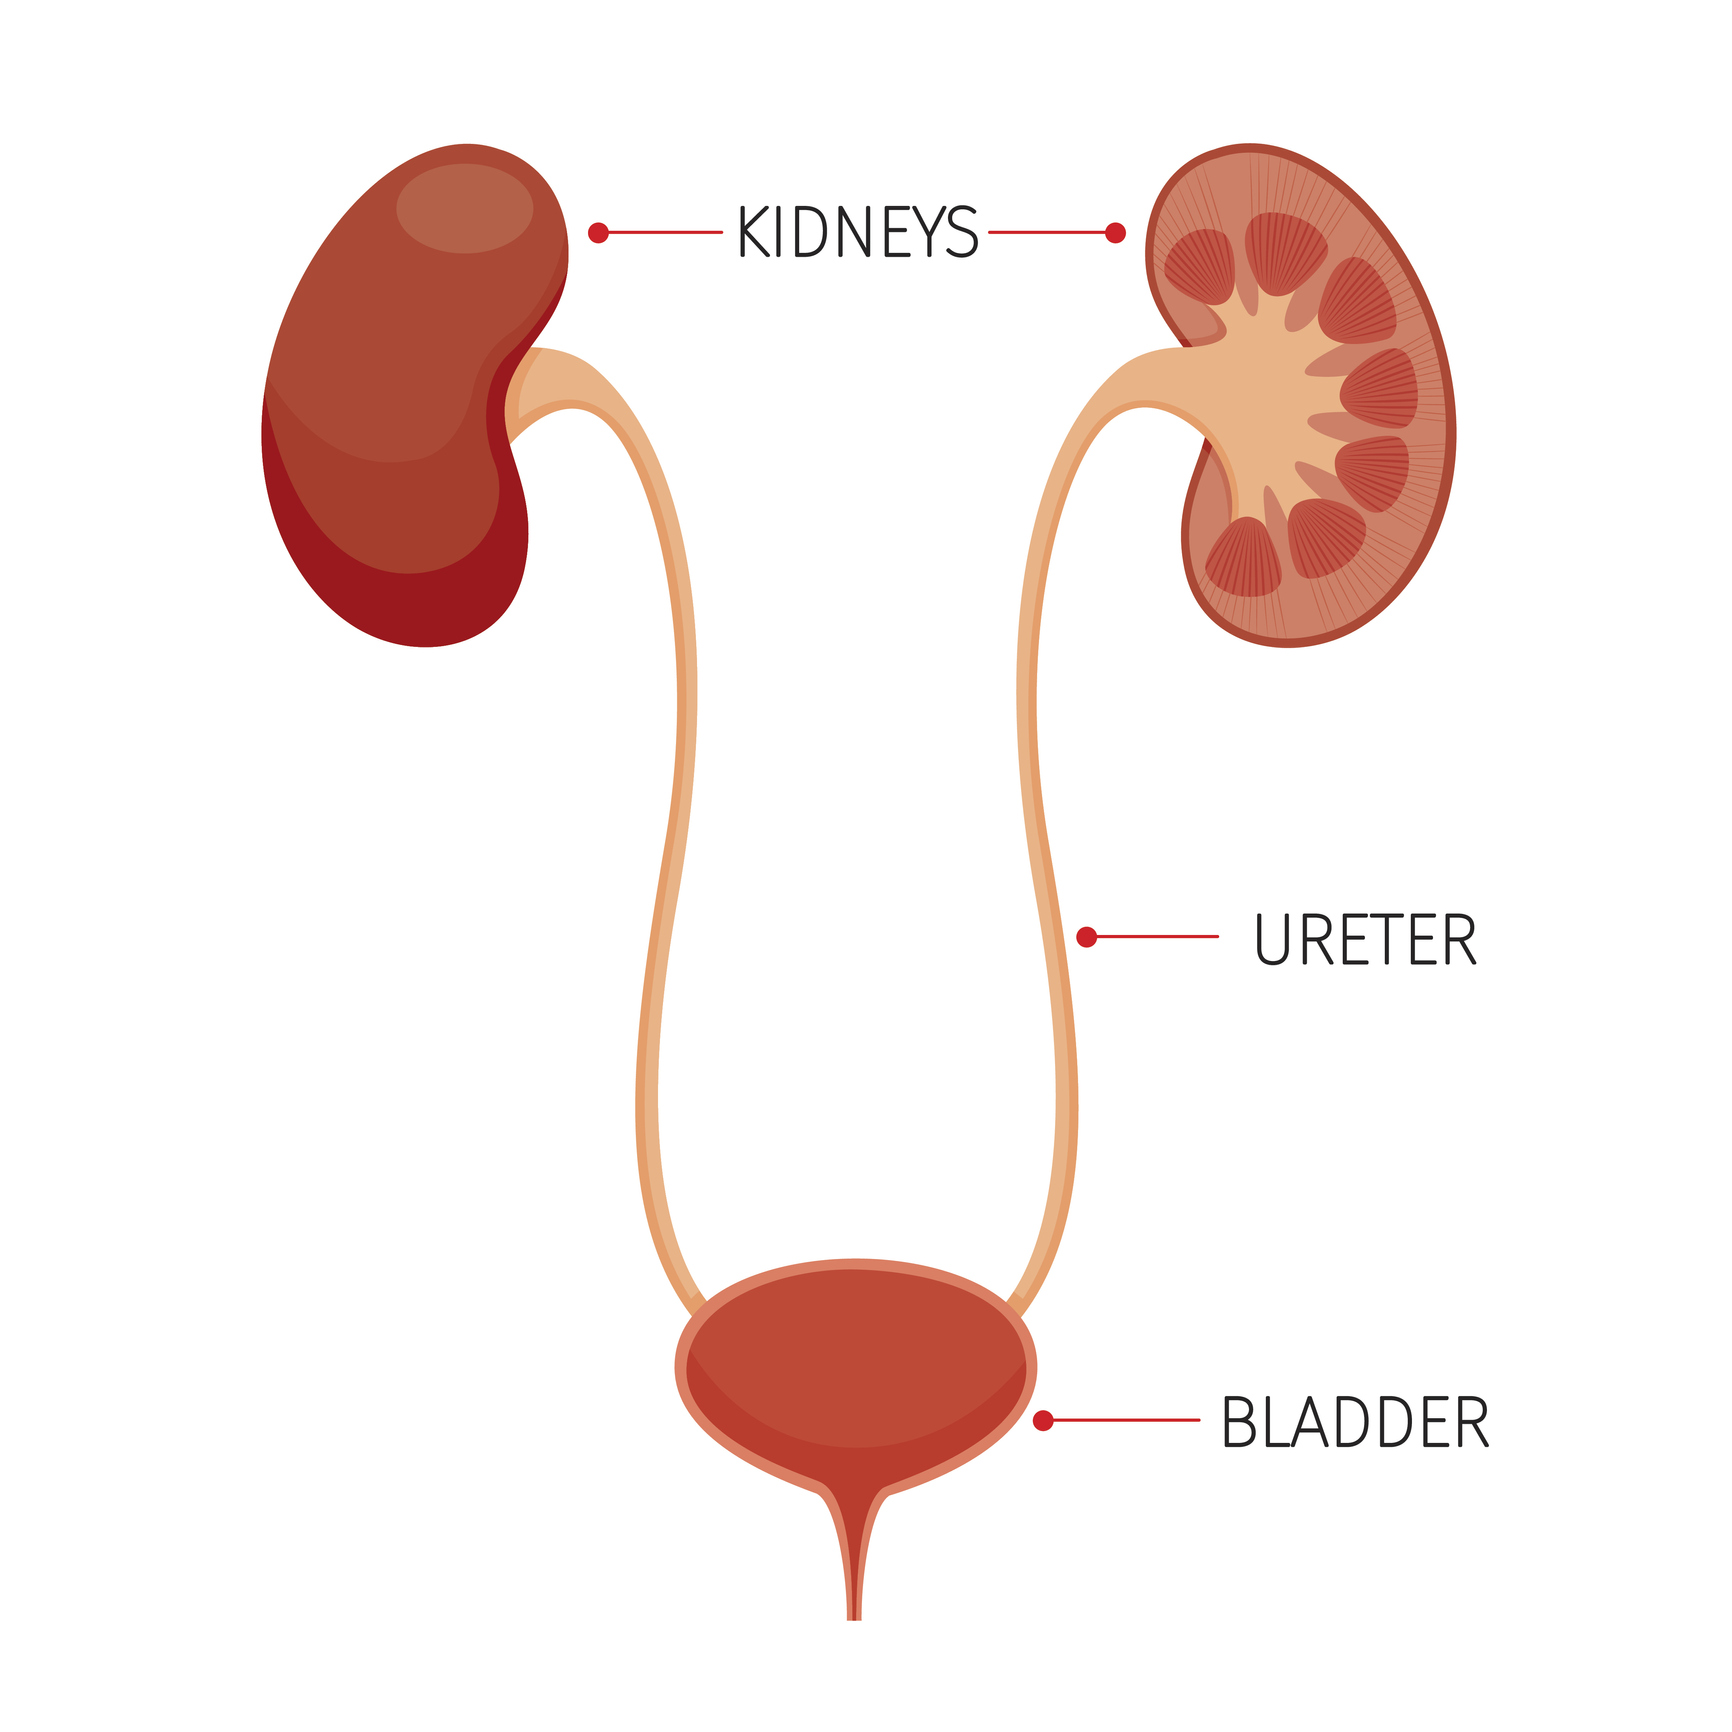

location of the bladder in the human body

Posts: location of the bladder in the human body